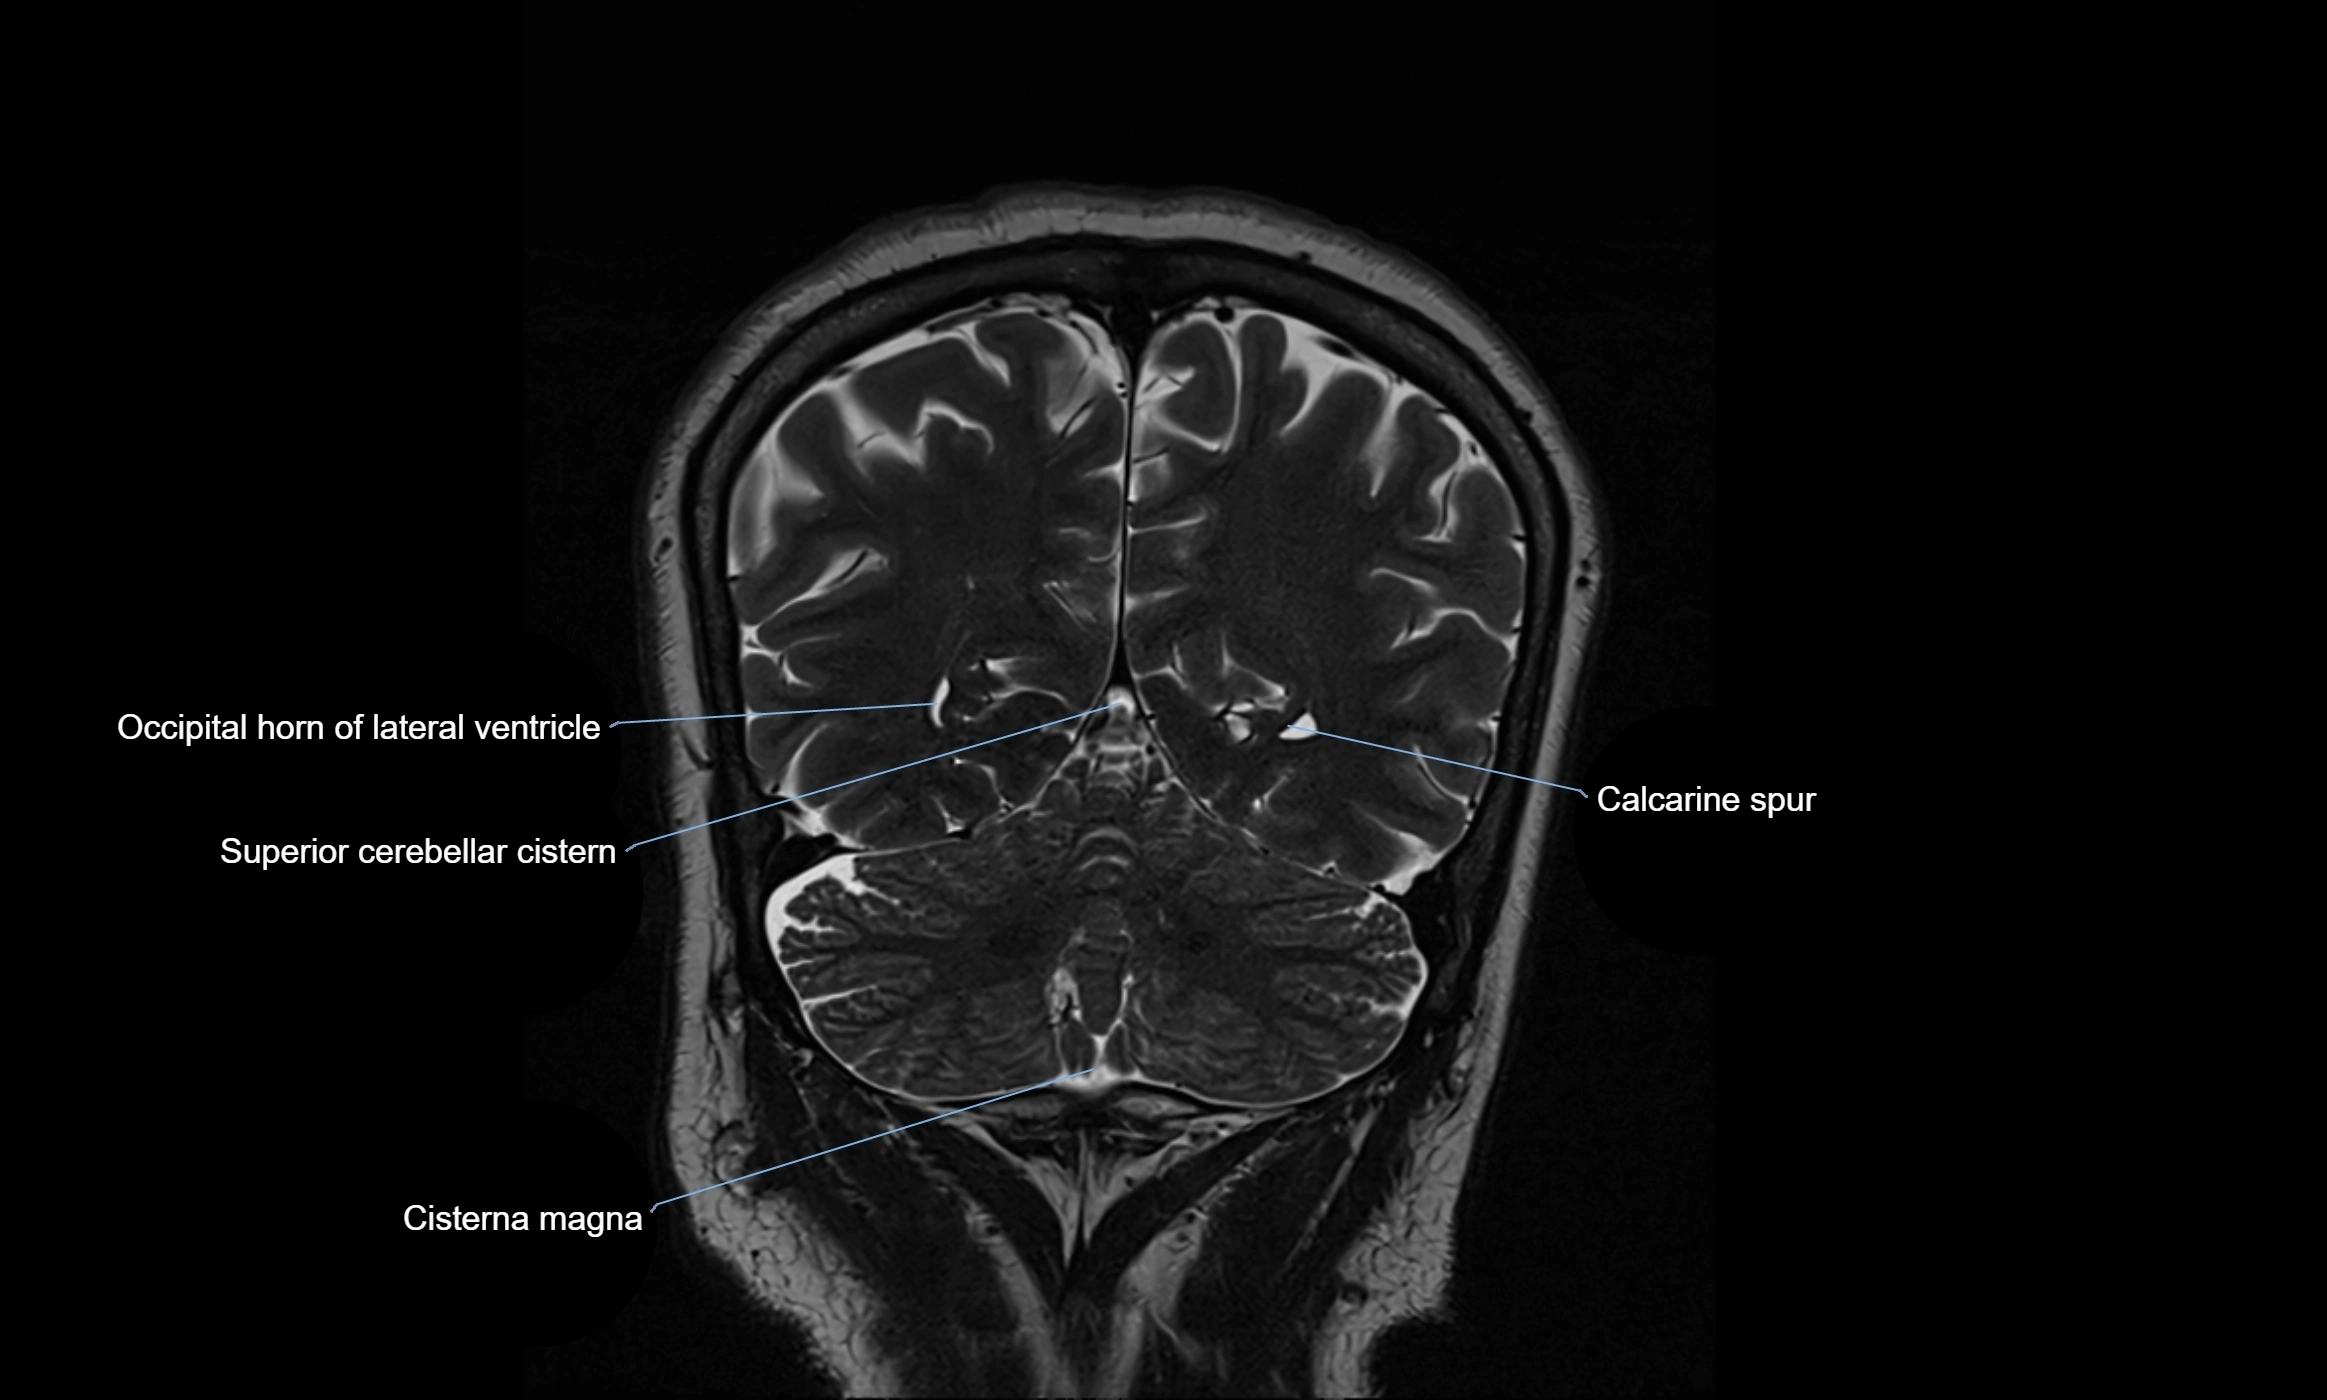

Ambient cistern

The ambient cistern is a paired, narrow, and elongated subarachnoid space located bilaterally along the lateral aspect of the midbrain. It serves as a conduit between the interpeduncular cistern anteriorly and the quadrigeminal cistern posteriorly. This cistern houses critical neurovascular structures, including parts of the posterior cerebral artery, superior cerebellar artery, trochlear nerve (cranial nerve IV), and the basal vein of Rosenthal. It plays an important role in the circulation of cerebrospinal fluid (CSF) and provides an anatomical corridor for various vessels and nerves passing around the midbrain.

MRI Appearance

• T2-weighted images:

• The cistern is hyperintense (bright) due to the high water content of CSF.

• Encapsulated vessels and nerves are seen as flow voids or hypointense lines within the bright background.